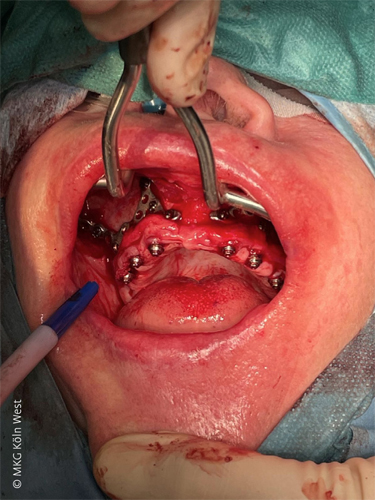

Die zweite Patientin (62 Jahre) wies ein parodontal stark geschädigtes Restgebiss im Oberkiefer auf. Nach Extraktion der nicht erhaltungswürdigen Zähne im Front- und Seitenzahnbereich war es intraoperativ zu einer ausgedehnten Mund-Antrum-Verbindung regio 16 (kommunizierende Kieferhöhle nach Zystektomie) gekommen. Die Patientin wünschte eine zeitnahe festsitzende Rehabilitation des Oberkiefers, wollte jedoch nach Möglichkeit keine vorgängigen Augmentationsverfahren durchlaufen. Nach ausführlicher Beratung über konventionelle augmentative Optionen (Sinuslift beidseits, umfangreiche laterale und vertikale Augmentation des Alveolarfortsatzes mit mehrmonatiger Heilungsdauer) entschied sich die Patientin für die Versorgung mit einem patientenspezifischen subperiostalen Implantat, das – analog zu Fall 1 – in Intubationsnarkose ambulant inseriert werden konnte. In diesem Fall wurde ein zweiteiliges Implantatgerüst für den zahnlosen Oberkiefer geplant, das insgesamt sechs Pfeiler für die prothetische Suprastruktur vorsah. Aufgrund der ausgeprägten Atrophie mit spitz auslaufendem Alveolarkamm war hier im Gegensatz zu Fall 1 zunächst eine gezielte Abtragung des Alveolarfortsatzes notwendig, um eine breitaufliegende, spannungsfreie Adaptation des Gerüsts zu ermöglichen. Die angefertigte Bohrschablone enthielt aus diesem Grund zusätzlich einen integrierten „Cutting Guide“ zur exakten Resektion der knöchernen Kammanteile in der Frontregion.

Nach erfolgter Alveolarkammglättung wurde jeweils rechts und links ein Implantatsegment passgenau aufgelegt und mit dem 1,5 mm MaxDrive-Schraubensystem fest am Knochen fixiert. Sechs transgingivale Pfeiler wurden durch entsprechende Stichinzisionen ausgeleitet und das Gerüst analog zu Fall 1 vestibulär mit verschobenem Bichat-Fettgewebe abgedeckt.